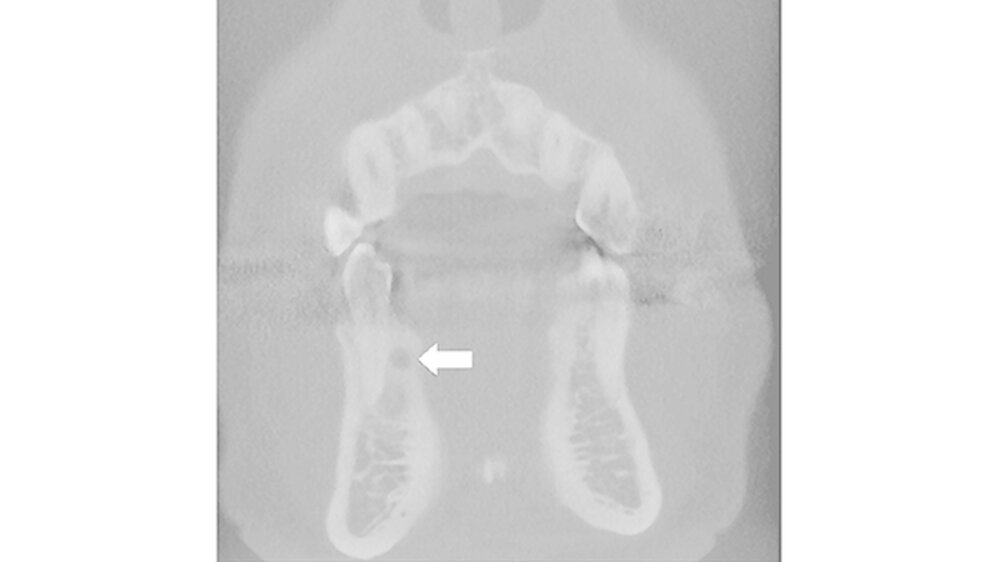

Die Patientin kam dann regelmäßig zu den Follow-ups, ohne dass klinische Symptome festgestellt wurden oder sie über Druckbeschwerden im betroffenen Bereich(Tabelle I)(4,6,8,10,12-49) geklagt hatte. Die beiden Zähne 33 und 34 blieben vital. Ein Röntgenbild zeigte nach zwei Jahren und 6 Monaten wieder strahlentransparente Veränderungen im OP-Bereich. Eine Digitale Volumentomographie (DVT) wurde kurz danach durchgeführt (Fig. 6).

Nach der genauen Diagnostik mithilfe des DVT war der vestibuläre Knochen zwischen den Zähnen 33 und 34 komplett neu aufgebaut. Ein runder strahlendurchlässiger Bereich von 3 mm Durchmesser auf Höhe des mittleren Drittels des Zahns 33 und eine durch den Tumor verursachte linguale Knochenexpansion wurden sichtbar.

SOT ist ein langsam wachsender Tumor. Die Behandlungsempfehlung der WHO entspricht einem konservativ-chirurgischen Eingriff (5). Allerdings ergab die vorliegende Studie auch, dass ein konservativer Ansatz, wie die Enukleation und die einfache Kürettage mit der Intention, die Vitalität der beteiligten Zähne zu erhalten, nicht ausreicht, um eine Wiederkehr zu verhindern. Dafür ist eine aggressivere Behandlung erforderlich. Nach der zweiten chirurgischen Behandlung erschien die Patientin für 2 Jahre und 6 Monate regelmäßig zum Follow-up, wo keine klinische Symptome auftraten, obwohl eine Cone Beam Computertomografie (CBCT) eine Veränderung lingual von Zahn 22 (Abb. 5) ergab. Es wurde jedoch kein zweites Rezidiv intraoperativ festgestellt.